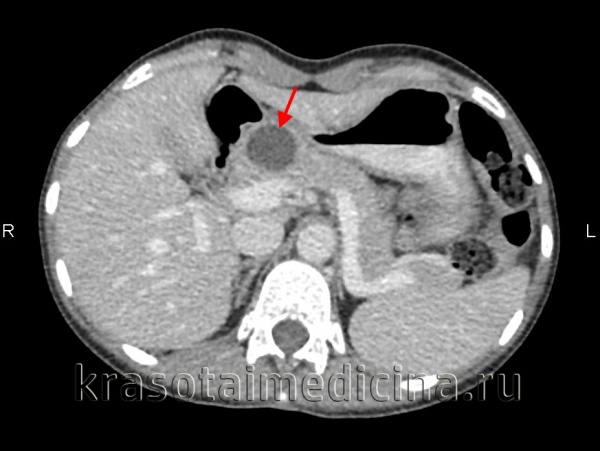

КТ органов брюшной полости. Псевдокиста поджелудочной железы у пациента после приступа острого панкреатита